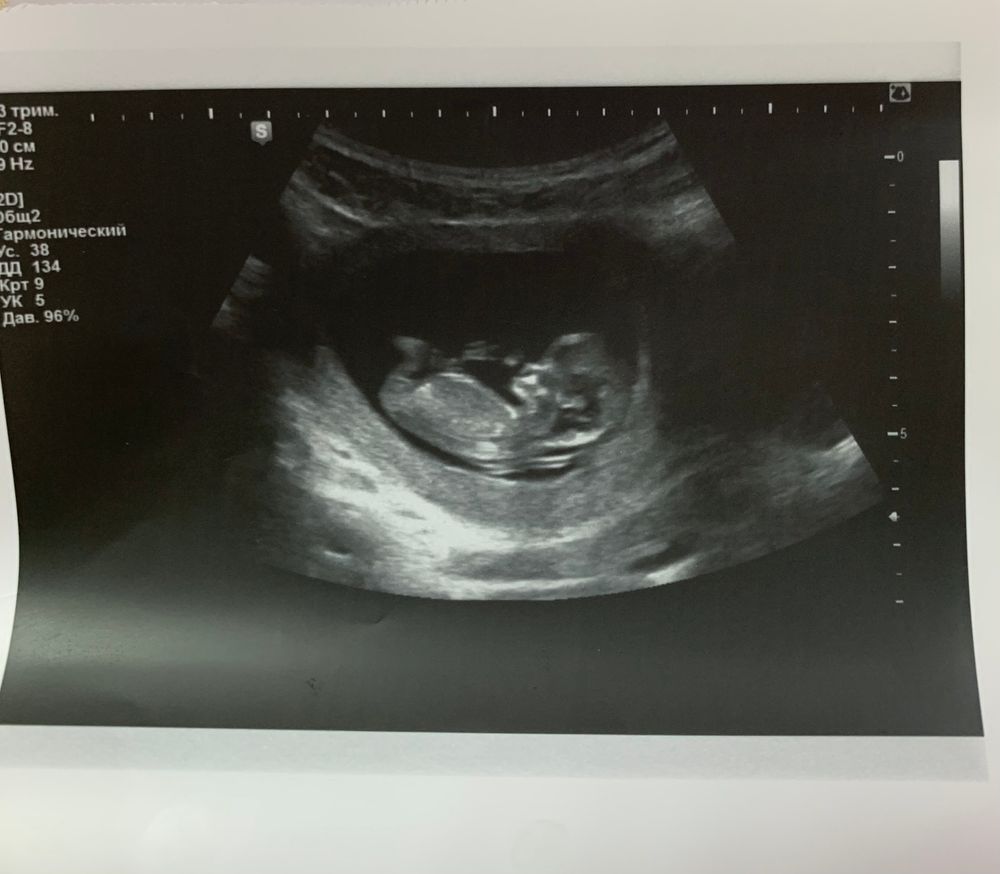

Новости с полей. Очередное узи для «успокоения» в 11+4 недель.

Стою на учёте в платном центре. В пакет входило одно простое узи в первом триместре. Я решила не упускать шанс и перед скринингом успокоить себя. В последнее время часто тянуло живот и спину, переживала из-за этого.

Но к моему большому счастью всё хорошо! И что самое главное - потихоньку уходит отставание. В 11,4 недель плод соответствует 11,2 недель. На узи был оочень активный))) Машет и руками, и ногами)